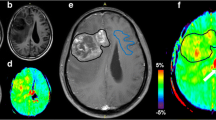

Hypermethylation of the O6-methylguanine-DNA-methyltransferase (MGMT) promoter in glioblastoma (GBM) is a predictive biomarker associated with improved treatment outcome. In clinical practice, MGMT methylation status is determined by biopsy or after surgical removal of the tumor. This study aims to investigate the feasibility of non-invasive medical imaging based “radio-genomic” surrogate markers of MGMT methylation status.

The imaging dataset of the RSNA-ASNR-MICCAI Brain Tumor Segmentation (BraTS) challenge allows exploring radiomics strategies for MGMT prediction in a large and very heterogeneous dataset that represents a variety of real-world imaging conditions including different imaging protocols and devices. To characterize and optimize MGMT prediction strategies under these conditions, we examined different image preprocessing approaches and their effect on the average prediction performance of simple radiomics models.

We found features derived from FLAIR images to be most informative for MGMT prediction, particularly if aggregated over the entire (enhancing and non-enhancing) tumor with or without inclusion of the edema. Our results also indicate that the imaging characteristics of the tumor region can distort MR-bias-field correction in a way that negatively affects the prediction performance of the derived models.